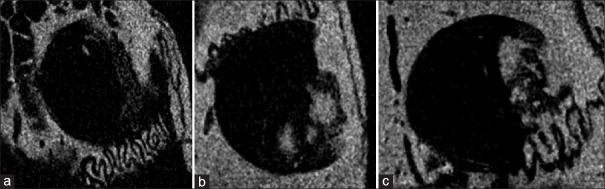

Materials and methods: Uniform craniotomy defects measuring 3 mm in diameter and 2 mm depth were performed in the parietal bones of 27 female albino Wistar rats, which were randomly divided into three groups: 1) a group receiving 100 mg/kg/day of oral metformin, 2) a group receiving 3 μg/kg/day of intraperitoneal exenatide, and 3) a control group receiving no medication. Bone volume and density at the defect site were evaluated using micro-CT scanning and analysis.

Results: Bone regeneration and the integration of newly formed bone into intact bone were assessed through histological and immunohistochemical examinations. In all three groups, the results showed no significant differences in bone volume, bone density, the presence of fibrous connective tissue, or the complete integration of the defect area into the bone tissue. However, the experimental groups exhibited significant differences in the number of osteoblasts (P = 0.007) and osteoclasts (P = 0.007) when compared to the control group.